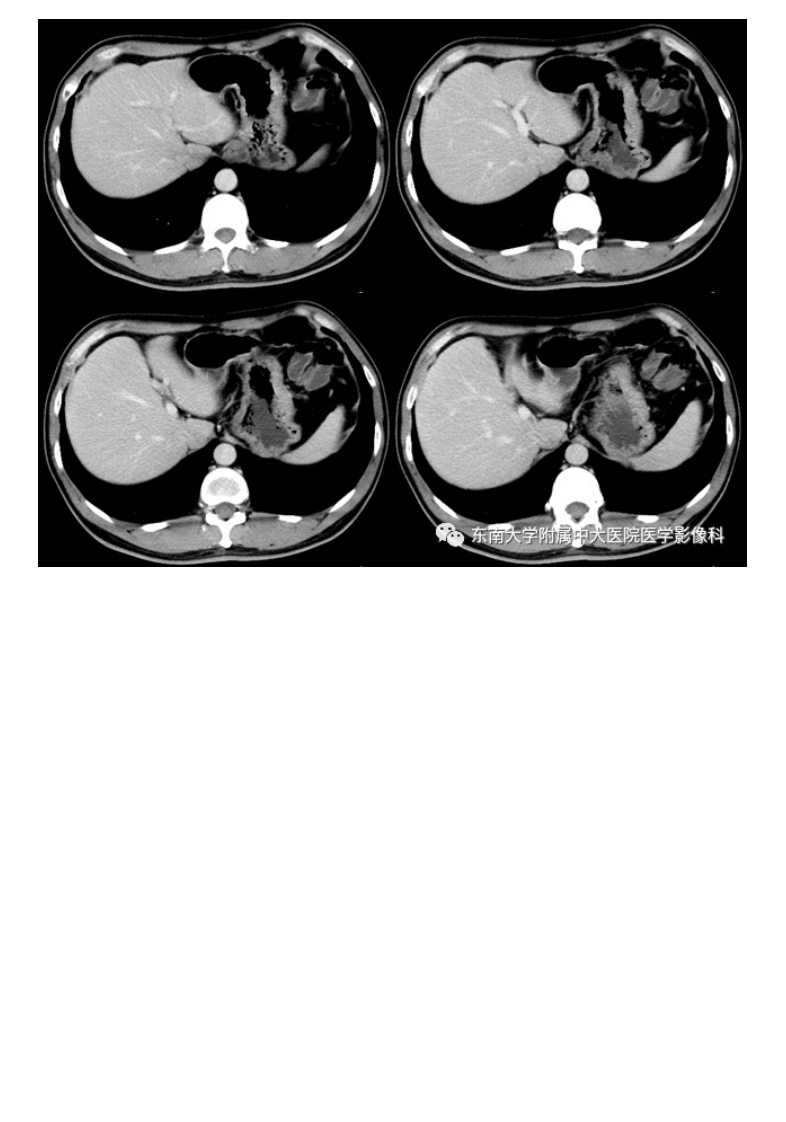

20210113_2【晨读结果公布】2021.01.13消化系统疾病——胃内异位胰腺.pdf